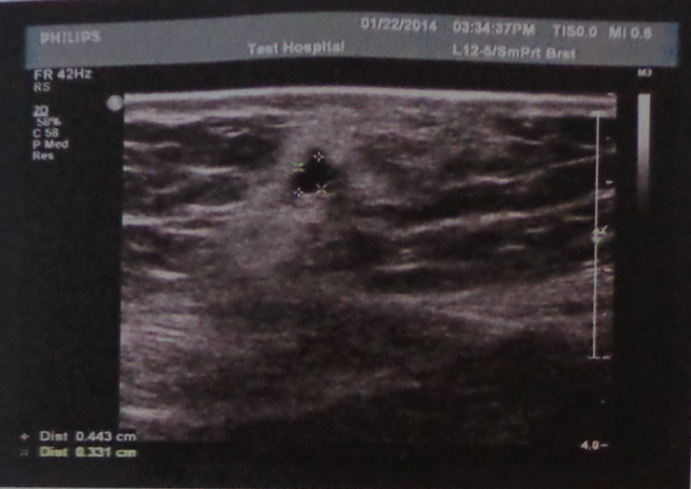

产后42天B超图,求专业人士解答? 剖宫产后42天B超图 ,问了医院就诊大夫几句,几乎什么也没说,就让回家吃点益母草,感觉那个大夫很业余啊,完全是在敷衍,有些不放心。超声提示:复壁皮下低回声区 点击展开 匿名用户 2014-02-01 17:06 为您推荐: 其他回答 病情分析: 您好,您的子宫双附件没什么问题 指导意见: 但是可能要重点关注下这个皮肤下的低回声区,建议您去找手术医生看下,主要是看下低回声区是什么东西。 匿名用户 2014-02-01 17:13 相关问题 我的产后42天B超单,能帮我解答下嘛? 产后六个月来月经,量不多,但断断续续一个多月了 做B超检查没问题,但还是没底啊,有专业人士帮诊诊吗? 产后42天没到做白带和B超检查能准吗